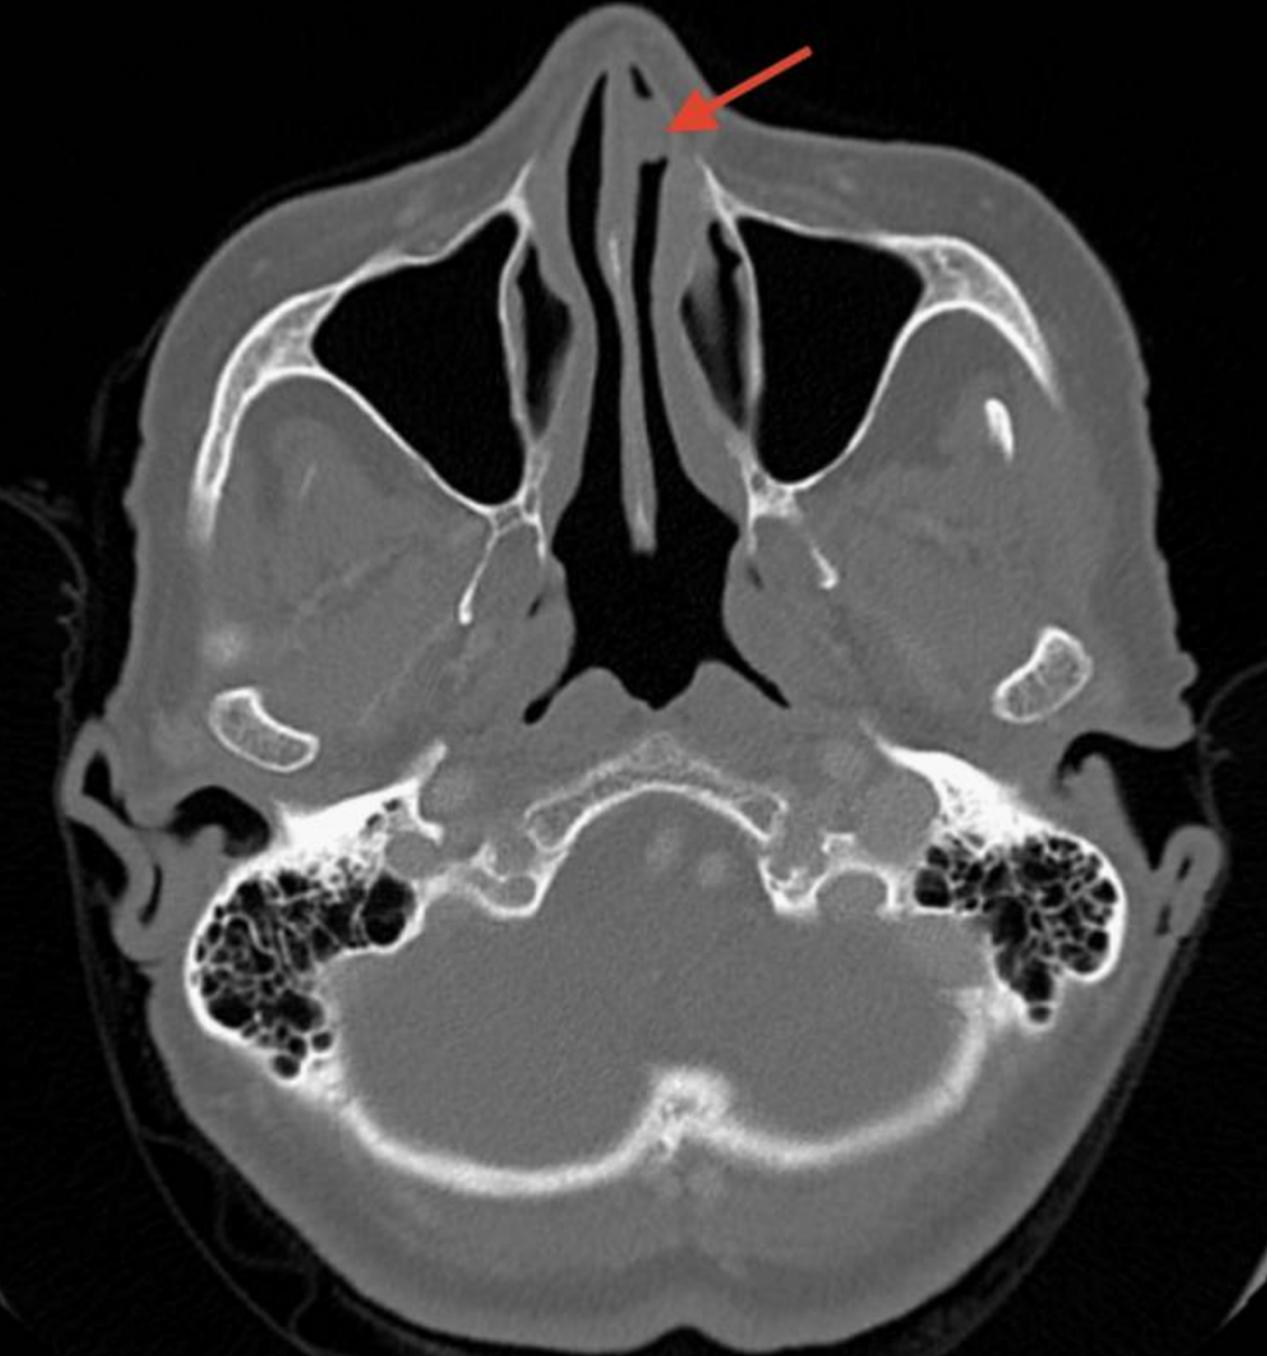

患者主诉左鼻孔出现鼻部不适,鼻腔通畅性降低,给药后(0.03%异丙托溴铵和生理盐水喷雾)从左鼻孔流出。鼻镜和CT扫描显示,左鼻孔内鼻前庭顶部有一个8x8毫米的肉质肿块(图1)。

图1 轴位CT扫描显示左鼻腔8x8mm肿物